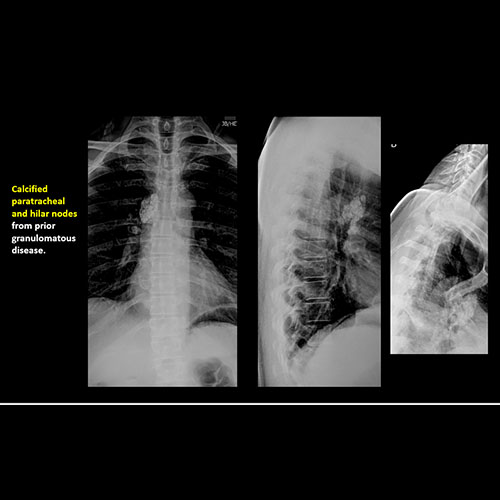

There are vascular calcifications or other soft tissue calcifications present. [Yes/No]